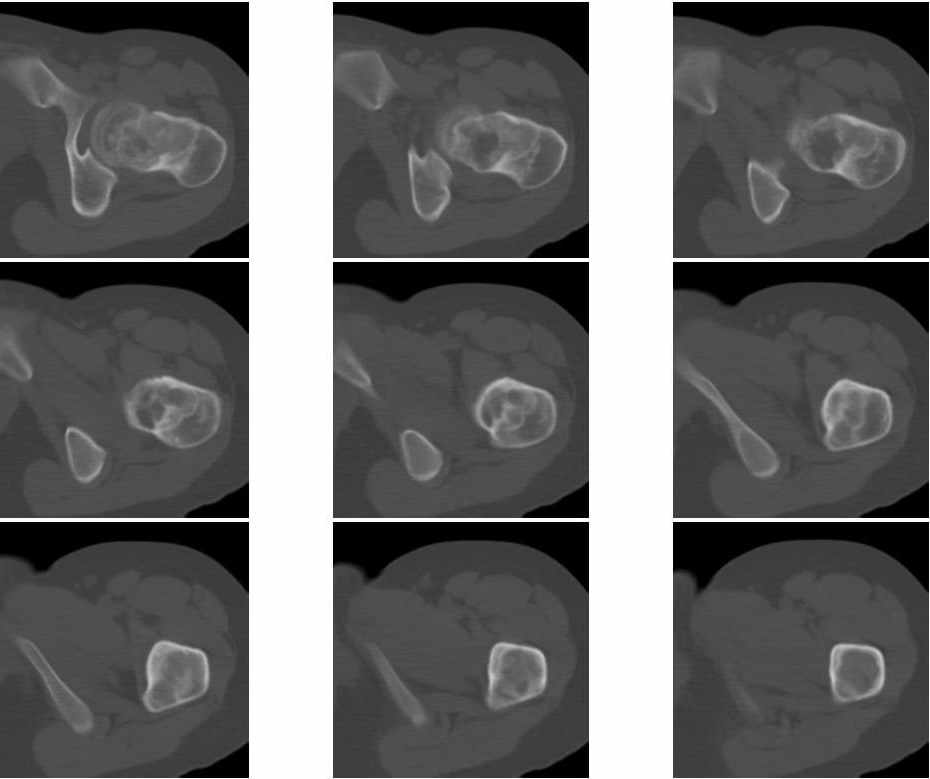

Молодая женщина 18 лет, последние 3 года стали беспокоить боли в левом тазобедренном суставе.

На рентгенограмме, утолщена шейка бедра и в шейке участок просветления. При КТ шейка утолщена на 9мм, в шейке полость24х21мм, стенки полости неровные и нечеткие, за пределы коркового слоя полость не выходит. Плотность содержимого полости 43 ед.Н. Предположительно должна быть солитарная киста шейки бедра, но смущает неровность и нечеткость контуров стенок. Ваше мнение господа? Какой предложите доступ для биопсии.Приложена первая серия снимков.

"У пациентки имеется гигантоклеточная опухоль области шейки и головки левого бедра.

Предпочтительный доступ для биопсии, по нашему мнению, - через большой вертел, не вскрывая суставной сумки.

Оперативное лечение обязательно, т.к. велика вероятность наступления патологического перелома.